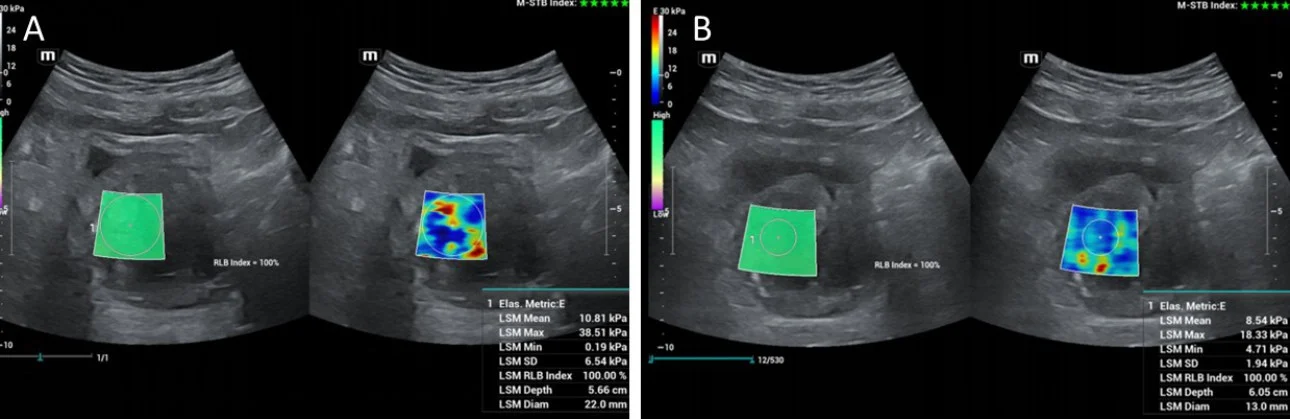

Importantly, CEUS can be applied in the angio-suite, during the PAE procedure, preferably at the end of the injection of the embolic material (Fig 2) to provide immediate feedback on the efficacy of PAE [2]. If this on-site CEUS study shows limited or no prostatic infarction, the interventionalist may attempt to inject more embolic material in the selected artery or to investigate for additional arteries feeding the prostate. Another CEUS technique that can also be performed intraoperatively entails intraarterial administration of diluted echo enhancer through the microcatheter, in order to delineate the area perfused by the selected artery [2,5]. This appears to be an effective preventive measure of non-target embolization. For intraprocedural monitoring of PAE (and of other endovascular interventions) the authors prefer a portable unit (M8,Mindray), which is a standard part of the equipment of the angio-suite and which, despite its compact size, rapidly provides high quality gray scale, color doppler as well as CEUS imaging during PAE.

Figure2: Representative transabdominal US and CEUS images acquired in the angio-suite, immediately post embolization of both prostatic lobes. Images are shown in a ‘split-screen’ mode with unenhanced, reference B-mode image on the right, and the corresponding CEUS image on the left. A: axial, B: sagittal plane. In both planes, CEUS confirms lack of enhancement (infarction) in the largest part of the prostate. Despite the often suboptimal imaging conditions, intraprocedural CEUS (during PAE) is feasible and increases the confidence of the interventionalist regarding the completeness of embolization